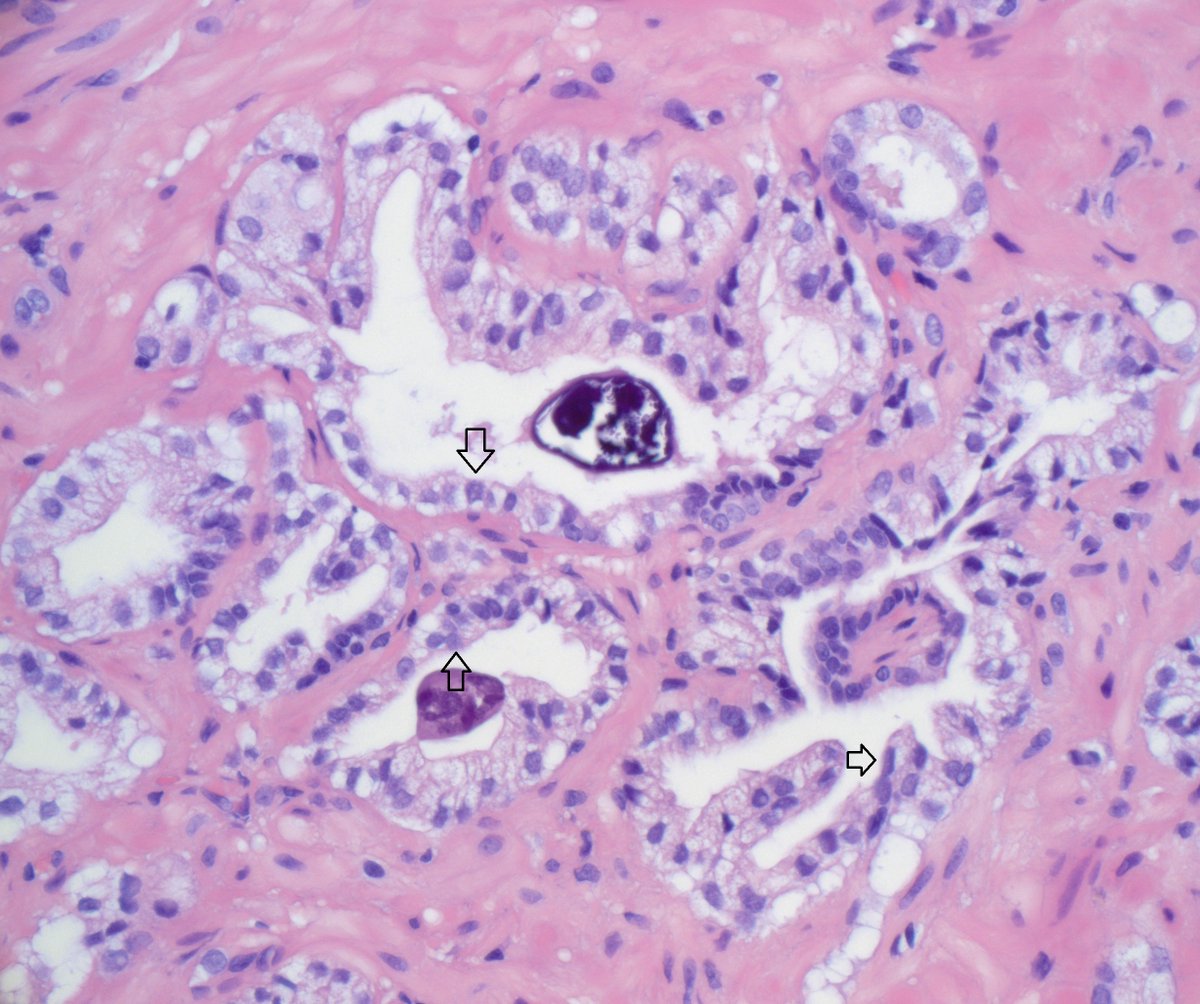

Indeed this is amebic colitis! Uncommon in western world (h/o travel is important). Characteristic flask shaped ulcers, amebic trophozoites often with ingested RBCs. #pathboards

Not my typical #gupath #gynpath post but an interesting one for trainees! Colon biopsy for GI bleed, clinical concern for IBD. #pathboards